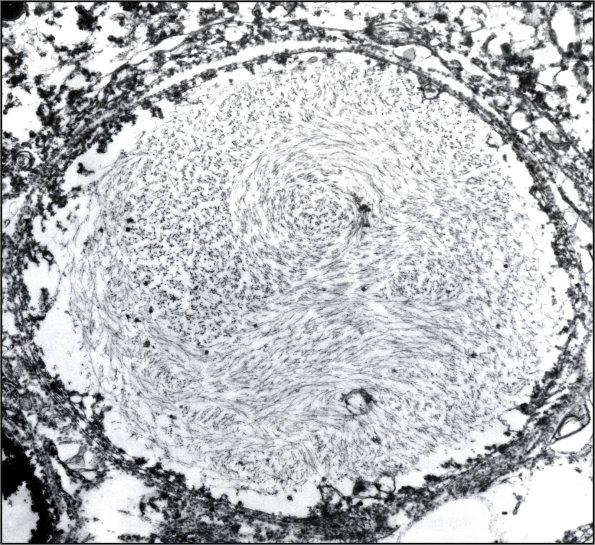

Dystrophic swellings correspond with neurofilament containing argyrophilic spheroids. (electron micrograph)